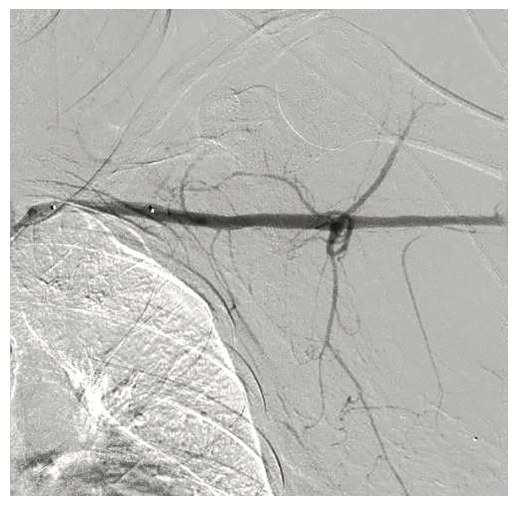

A 54-year-old female with a history of peripheral arterial disease (PAD), tobacco abuse, diabetes, severe chronic obstructive pulmonary disease (COPD), obesity, hypertension, and hyperlipidemia presented to an outside hospital with a non-ST-elevation myocardial infarction (NSTEMI). Subsequent left heart catheterization revealed a chronic total occlusion (CTO) of the left anterior descending coronary artery (LAD) and left circumflex (LCx), with a 95% ostial ramus and a patent right coronary artery (RCA) with right to left collaterals (Figures 1-2). Initial ejection fraction by ventriculogram was approximately 30-35%. She was turned down for surgery and subsequent studies revealed viable myocardium; therefore, she was scheduled for percutaneous revascularization with mechanical circulatory support using an Impella left ventricular assist device (Abiomed). She was found to have bilateral occlusion of her iliac stent (Figure 3). It was decided to revascularize at least one of her occluded iliac arteries, and then use the femoral and radial approach for dual access in order to recanalize the CTO. The axillary artery would be used for the Impella, rather than advancing the 14 French (Fr) sheath through a freshly stented artery. The right iliac artery was revascularized and she was brought back to revascularize the left system.

The right groin was accessed using fluoroscopic guidance. A micropuncture sheath was placed and upsized to a 7 French, 45 cm Destination sheath (Terumo) in the right groin. We accessed the right radial, but could not get good flow. Therefore, we ended up using the ulnar artery with ultrasound guidance and placed a Terumo 5/6 Slender sheath in the ulnar artery. We proceeded to access the left axillary artery. We placed a Judkins right (JR)4 catheter in the left subclavian and did a selective angiogram, documenting the location of the thoracoacromial artery and circumflex humeral (Figure 4); then using a Chiba biopsy needle (Cook), accessed the axillary artery and placed a 5-French 30 cm sheath (Cook)(Figure 5). We used the 15 cm biopsy needle to allow us a shallow angle of approach with the patient’s body habitus and to avoid “kinking” the sheath. We then switched out for the Lunderquist wire (Cook Medical), placed an 8 Fr sheath, and performed a pre-close using two Perclose devices (Abbott Vascular) (Figure 6).